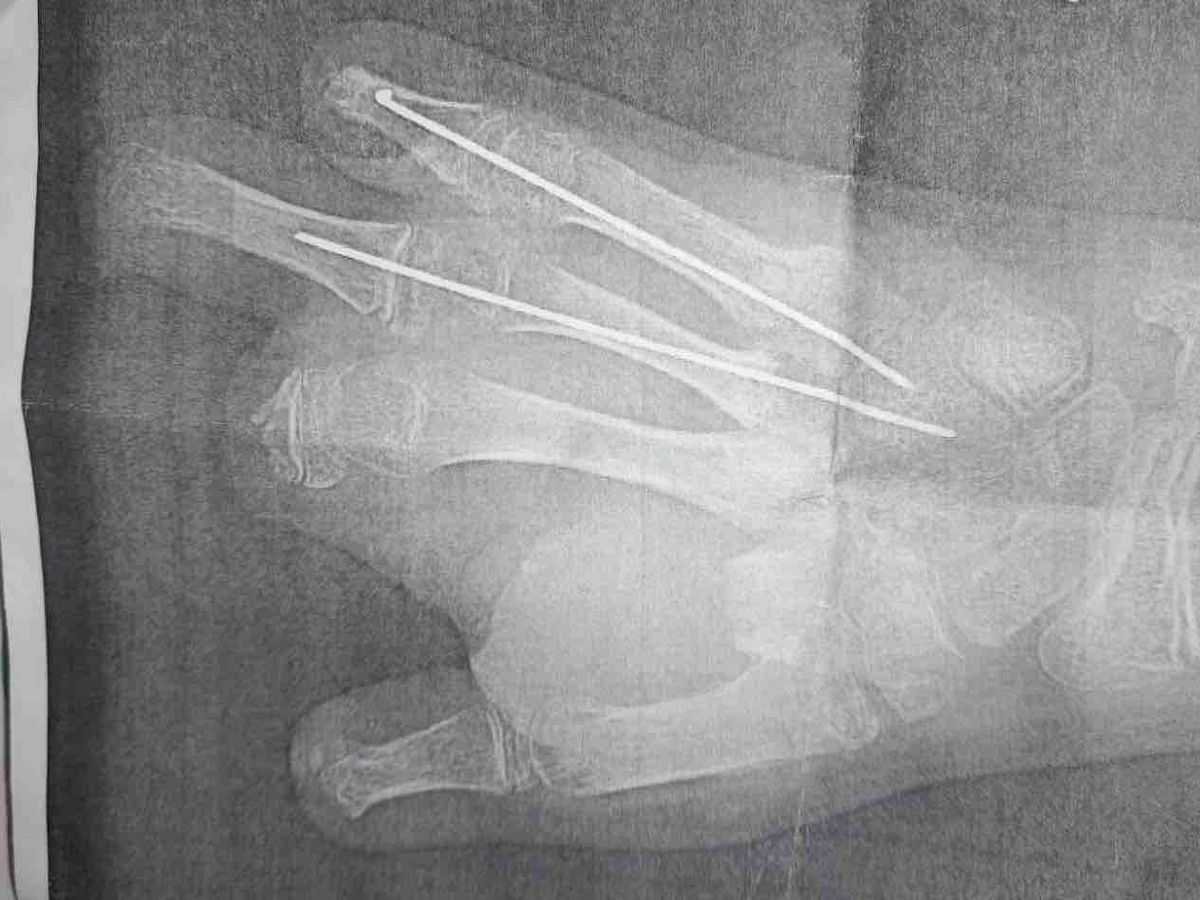

On June 23, my family’s world was turned upside down. My 12-year-old little brother was severely injured when a firework exploded in his hand. In an instant, he lost most of the fingers on his right hand—his dominant hand. The injuries were so severe that he had to be airlifted by helicopter to the hospital, where doctors rushed him into surgery.

He spent the next two weeks in the hospital, undergoing multiple surgeries in an effort to save what they could and begin the long road to recovery.